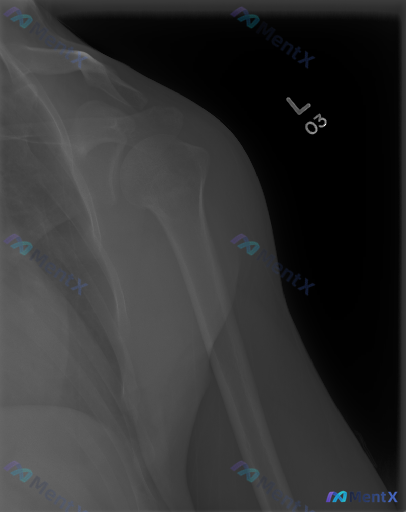

整理了一份左侧肩部正位X光片的资料,先看影像表现: - 肱骨近端、肩胛骨、锁骨远端骨皮质连续,未见明确骨折线/脱位 - 骨密度均匀,无明显骨质破坏或硬化 - 盂肱关节、肩锁关节间隙正常,无明显骨赘形成 - 肩周软组织无明显肿胀,冈上肌腱止点附近未见明确钙化灶 简单说:单看这份X光,骨性结构基本是“阴...

整理到一个影像讨论的情况,有点意思,也很容易踩坑: - 资料是一张肩部正位X光片 - 影像分析看下来:肱骨近端、肩胛骨、锁骨骨皮质连续,肩锁/盂肱关节对位好,间隙正常,没有明显骨折、脱位、增生、骨破坏,软组织也没看到肿胀或钙化 - 但有个核心矛盾:明确提示这份图像/病例存在异常 想问大家: 1. 第...